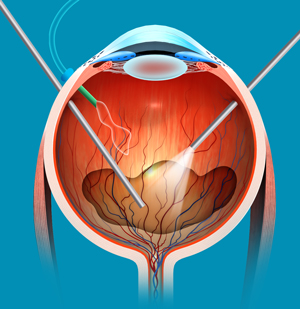

What are Vitreo Retinal Surgeries?

Vitreo Retinal Surgeries are specialized procedures that address problems of the retina and vitreous — the clear, gel-like substance inside the eye. These surgeries are crucial in treating various retinal diseases that can lead to vision loss if not addressed timely.

- Pars Plana Vitrectomy